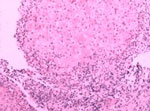

糜烂性胃炎是临床上常见的消化道疾病之一,根据其病程发展分为急性糜烂性胃炎和慢性糜烂性胃炎。武汉糜烂性胃炎治疗好医院是哪家?

武汉博仕中医肛肠医院的超导光纤维胃镜是通过百倍放大的图像信息,把食管、胃、十二指肠降部的粘膜病变更加直观展现出来,它具有影像质量好、屏幕 画面大、图像清晰、分辨率高、弯曲角度大、操控灵活等优点,通过它,医生能够用肉眼直接观察到消化道的内部情况,能够发现诸如溃疡、息肉、憩室炎症等病 变,还能看清黏膜的充血、水肿以及色泽改变等细微变化,锁定病症,为医生制定详细的治疗方案奠定了基础。